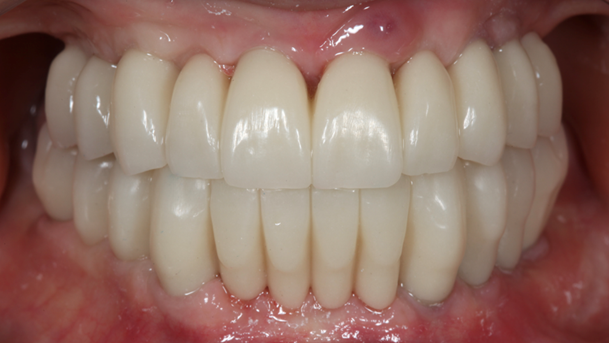

- Courtesy of Dr. Jong Cheol Kim, Korea

Effective R2STUDIO in complex tooth positioning